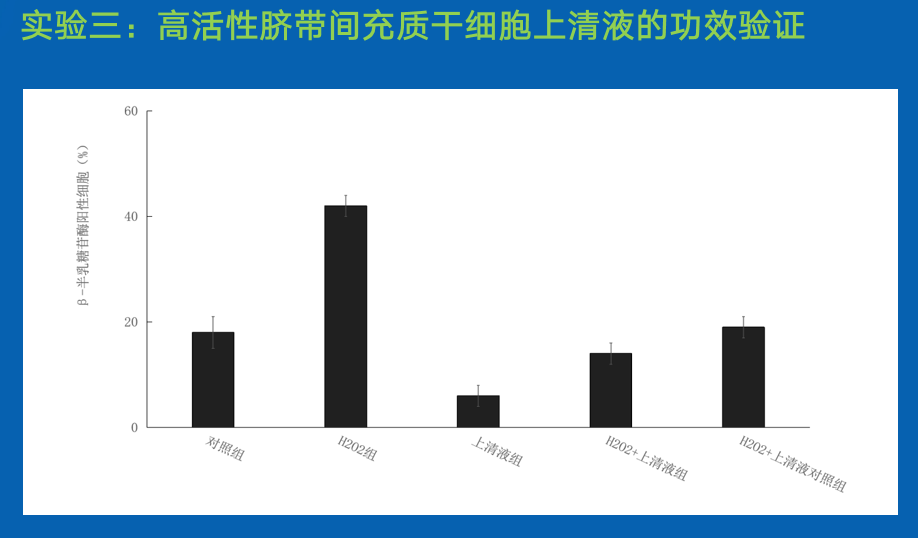

结论:

脐带间充质干细胞培养上清液可抑制H2O2诱导的成纤维细胞衰老进程,采用D25-F3多肽培养脐带间充质干细胞获得上清液具有更强的抑制HDF衰老的特性。